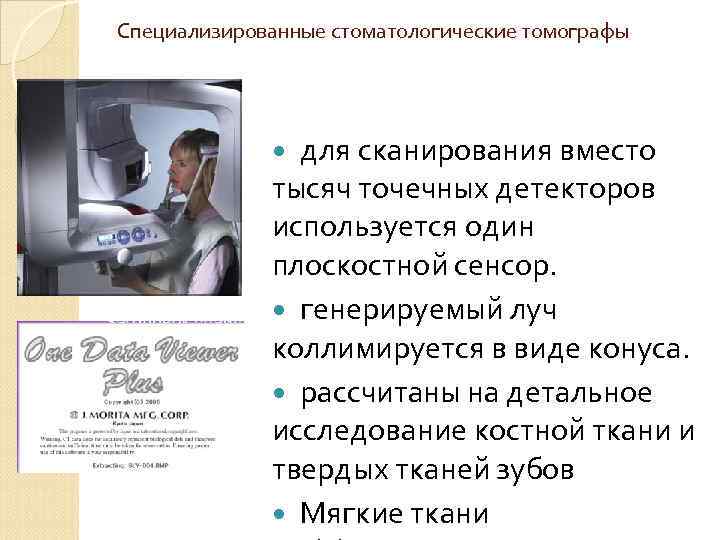

Специализированные стоматологические томографы для сканирования вместо тысяч точечных детекторов используется один плоскостной сенсор. генерируемый луч коллимируется в виде конуса. рассчитаны на детальное исследование костной ткани и твердых тканей зубов Мягкие ткани

Специализированные стоматологические томографы для сканирования вместо тысяч точечных детекторов используется один плоскостной сенсор. генерируемый луч коллимируется в виде конуса. рассчитаны на детальное исследование костной ткани и твердых тканей зубов Мягкие ткани